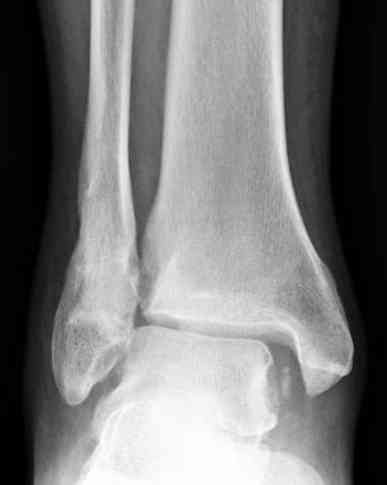

Больному всего 42, сохранный сустав, за 1.5-2 месяца сустав еще не успел "выработаться".

В данный момент больной из категории "фиксируемых

переломов" переходит в категорию "плановых", т.е.

сейчас без спешки, согласно "стандартных"

рентгенологических обследований можно планировать

восстановление.

К тому времени несросщиеся кости консолидируются,

потом легче произвести расчеты по высоте малоберцовой и выбору типа остеотомии.

Здесь представлено решение похожей проблемы. Больной в течение года лечился консервативными мерами, и боли в голеностопе были основным показанием к операции.

Проведена обычная стандартная процедура по исправлению неудовлетворительного состояния голеностопного сустава, где кроме удлинения малоберцовой с применением compression tension device за проксимальный конец пластины, проведено замещение трикортикальным графтом из крыла, освобождение синдесмоза и медиальной щели от

фибротических масс с фиксацией.